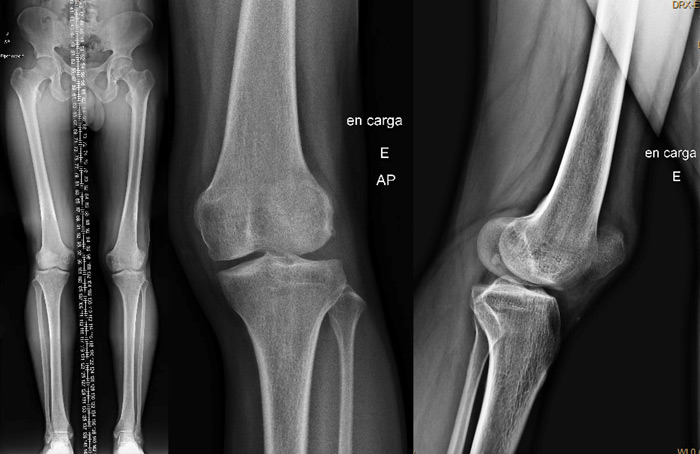

Pre-operative X-rays

Pre-op X-rays

Pre-operative measurements

• HKA = 180°

• TT-TG = 24 mm

• Femoral neck anteversion (FNA) = 27.5°

• Dejour type C trochlear dysplasia